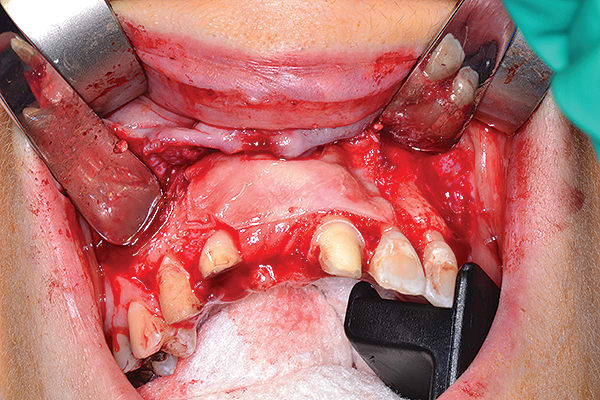

Figure 5

Figure 5 Ridge augmentation was completed with the use of a tenting screw (KLS Martin, www.klsmartin.com), recombinant human bone morphogenetic protein-2 (rhBMP-2) (Medtronic, www.medtronic.com), plasma rich in growth factors (PRGF) (BTI, www.bti-biotechnologyinstitute.com), collagen membrane, and a mixture of cortico-cancellous allograft and xenograft.

Figure 6

Figure 6 Ridge augmentation was completed with the use of a tenting screw (KLS Martin, www.klsmartin.com), recombinant human bone morphogenetic protein-2 (rhBMP-2) (Medtronic, www.medtronic.com), plasma rich in growth factors (PRGF) (BTI, www.bti-biotechnologyinstitute.com), collagen membrane, and a mixture of cortico-cancellous allograft and xenograft.